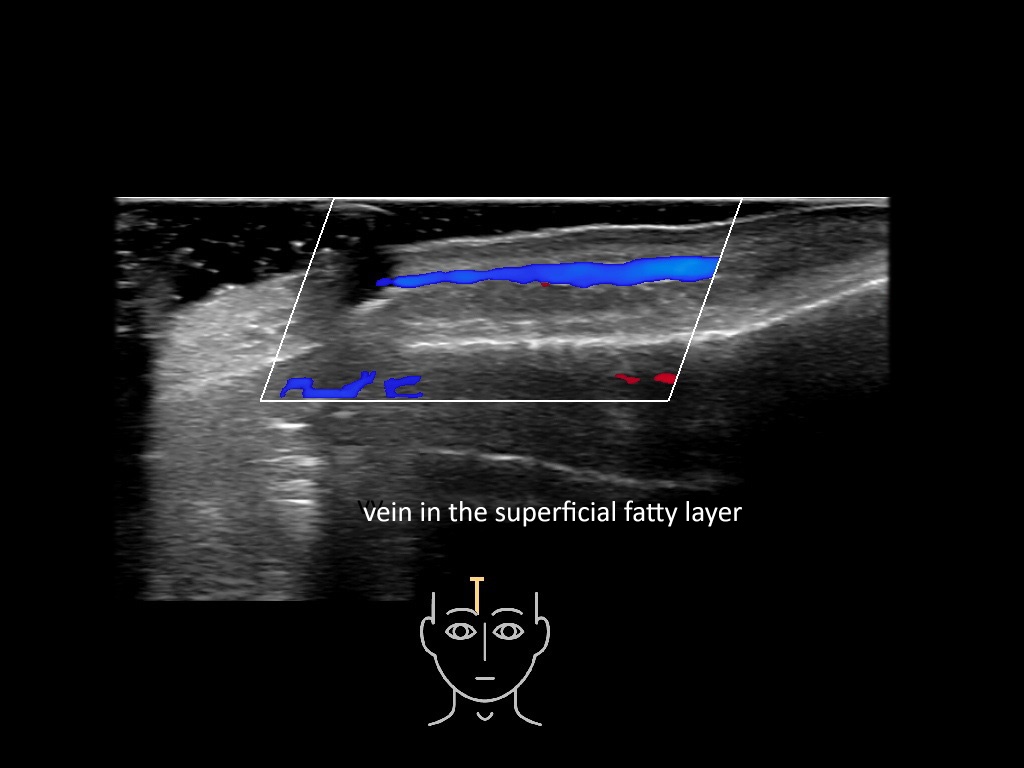

In this section you will learn more about the different layers of the face with the use of ultrasound. When you click on the secondary ultrasound image, you will see the different structures as an overlay. This will help to train yourself to recognize the different layers of the face.

Study the first image to recognize the different layers. If you are sure about the layers, swipe to the second image to view the answer (if applicable).